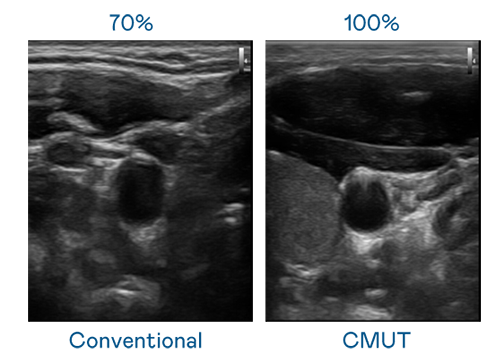

LEYU官網(wǎng)運(yùn)用 TFT 陣列 (Array) 制程延伸尖端感測技術(shù),開發(fā)出多種感測元件的LEYU官網(wǎng)。高解析度、品質(zhì)穩(wěn)定且可量產(chǎn)的 CMUT 元件,可制作高解析度超音波探頭、貼片型探頭,對(duì)病患實(shí)施精準(zhǔn)檢測與長時(shí)間生理監(jiān)測。